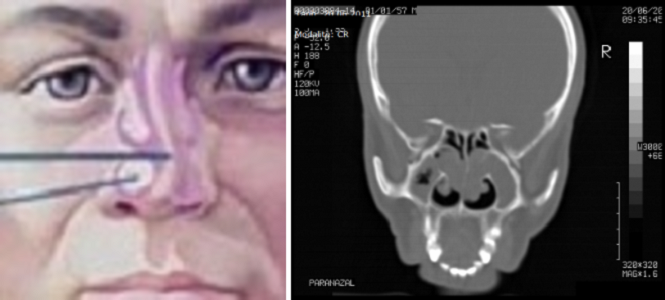

Endoskopik Sinüzit Ameliyatı

Sinüzit baş ağrısı, burun tıkanıklığı, geniz akıntısı ve bazen de burun kanamasıyla kendini gösteren yaygın bir hastalıktır. Önceleri ağız içinden kesiler yapılarak yapılırdı